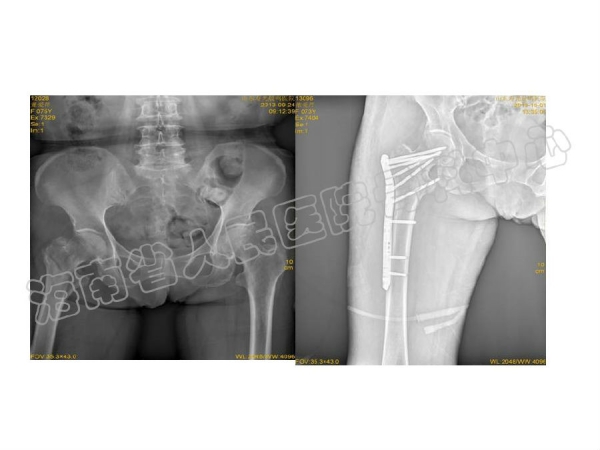

2014-04-14 文章来源:海南省人民医院骨科中心 沈宁江 我要说